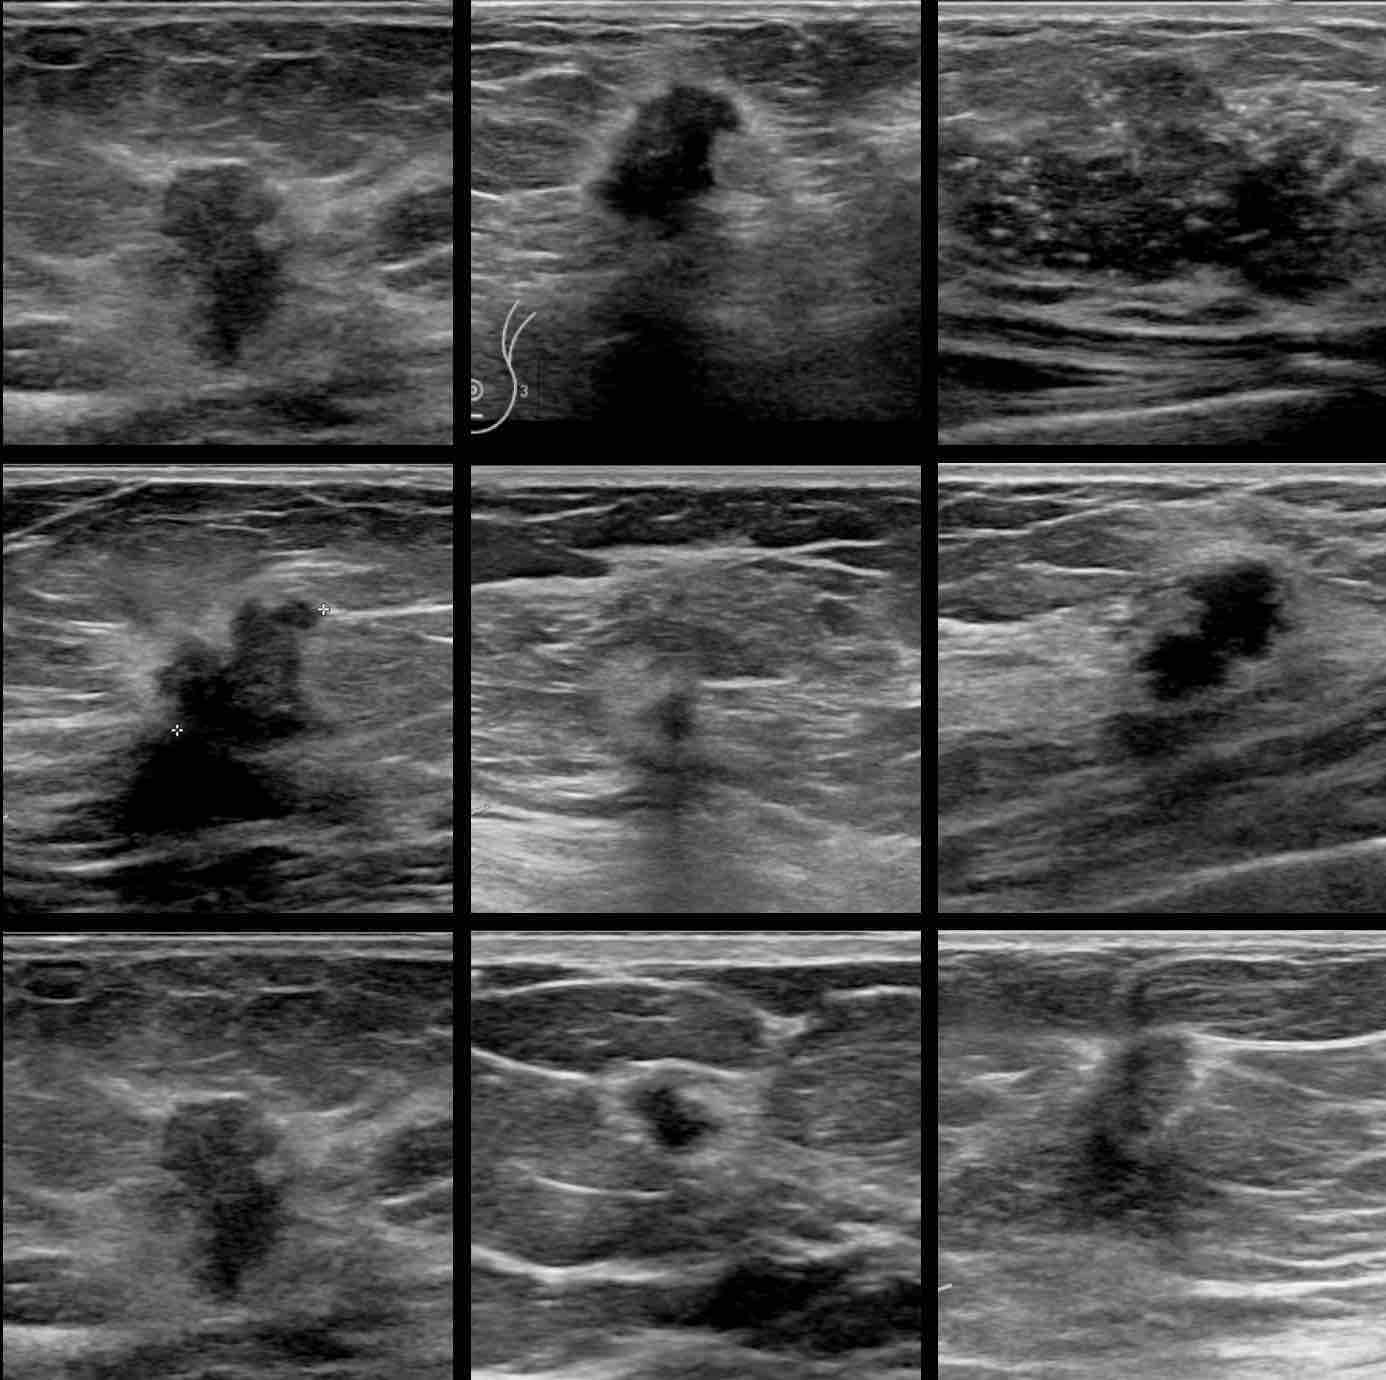

Nhân trong siêu âm tuyến vú là một vùng mô bất thường xuất hiện dưới dạng khối u nhỏ trong mô vú. Khi thực hiện siêu âm, nhân được nhận diện qua hình ảnh là một vùng có mật độ và màu sắc khác biệt so với mô vú xung quanh. Có hai loại nhân chính thường gặp:

- Nhân rắn (solid nodule): Là khối u cứng, không chứa dịch, có thể là một u lành tính như fibroadenoma hoặc trong trường hợp xấu hơn có thể là khối u ác tính.

- Nhân chứa dịch (nang - cystic nodule): Đây là các khối u chứa dịch, phổ biến hơn và thường không gây ra vấn đề sức khỏe nghiêm trọng.

- U xơ tuyến vú: Đây là loại u lành tính phổ biến ở phụ nữ trẻ. Nhân u xơ có thể nhiều khối u nhỏ và nang trong mô vú, có hình tròn hoặc bầu dục, bề mặt nhẵn, ranh giới rõ ràng, không xâm lấn vào các mô xung quanh và không gây đau. U xơ tuyến vú không liên quan đến nguy cơ ung thư vú nhưng có thể to dần lên theo thời gian.

- U nang vú: Nhân u nang thường chứa đầy dịch, tạo ra hình ảnh đen hoặc tối trên siêu âm và không có tổ chức mô vú bên trong. U nang có viền rõ ràng, dễ phân biệt với các mô xung quanh. Các nang thường lành tính, có thể tự biến mất và không gây ra vấn đề sức khỏe nghiêm trọng nào.

Nhân lành tính có biểu hiện ranh giới rõ ràng, hình tròn hoặc bầu dục và dễ phân biệt với các mô xung quanh.

Những đặc điểm của nhân ác tính thường gặp trên siêu âm tuyến vú:

- Ranh giới nhân không rõ ràng: Một trong những đặc điểm dễ nhận biết nhất của nhân ác tính là viền không rõ ràng. Những khối u này có thể có hình dạng gồ ghề, không đều và có dấu hiệu xâm lấn vào các mô xung quanh.

- Hình dạng bất thường: Nhân ác tính thường có hình dạng bất đối xứng, có thể có tua gai hay gập góc.

Nhân ác tính thường có hình dạng bất thường và ranh giới không rõ ràng.